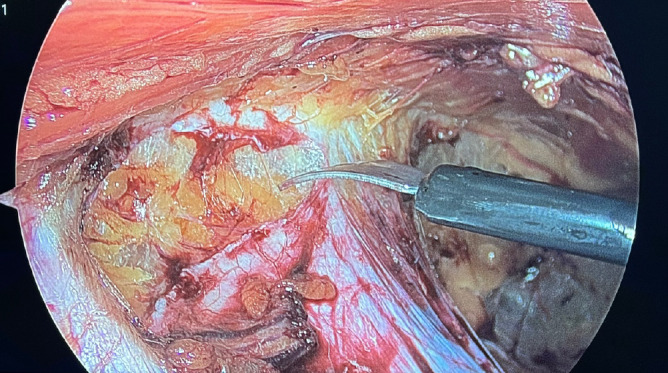

Objective: The treatment of scrotal hernias may vary according to the surgeon's experience. Although open anterior approaches are mostly preferred, specialized hernia surgeons prefer laparoscopic approaches. The study evaluated the safety and efficacy of the laparoscopic enhanced view-totally extraperitoneal (eTEP) technique and the laparoscopic totally extraperitoneal (TEP) technique in treating scrotal hernias.

Material and methods: The retrospective cohort study compared patients with unilateral scrotal hernia who underwent eTEP or TEP from November 2022 to October 2023. The two groups were compared in demographic characteristics and operative and postoperative data. The main result of this study was the recurrence rate.

Results: A study analyzed 54 patients: 30 underwent the eTEP technique, and 24 underwent the TEP technique. No significant difference was observed between the groups regarding recurrence rates, incidence of chronic pain, time of the surgical procedure, length of stay, time taken to resume daily activities, pneumoperitoneum occurrence, and complications, particularly hematoma and seroma formation. Patients were followed up for an average of 19 months (±5.2).

Conclusion: The comparison of the eTEP technique to traditional TEP for scrotal hernia repair has not demonstrated any conclusive evidence of the superiority of eTEP. The outcomes associated with the eTEP technique were found to be comparable to those of TEP, with an average follow-up period of 19 months. Similar to TEP, the eTEP technique demonstrates both safety and feasibility in the management of scrotal hernias. Furthermore, it is necessary for prospective randomized studies to compare these two techniques directly, specifically in the realm of scrotal hernia repair.